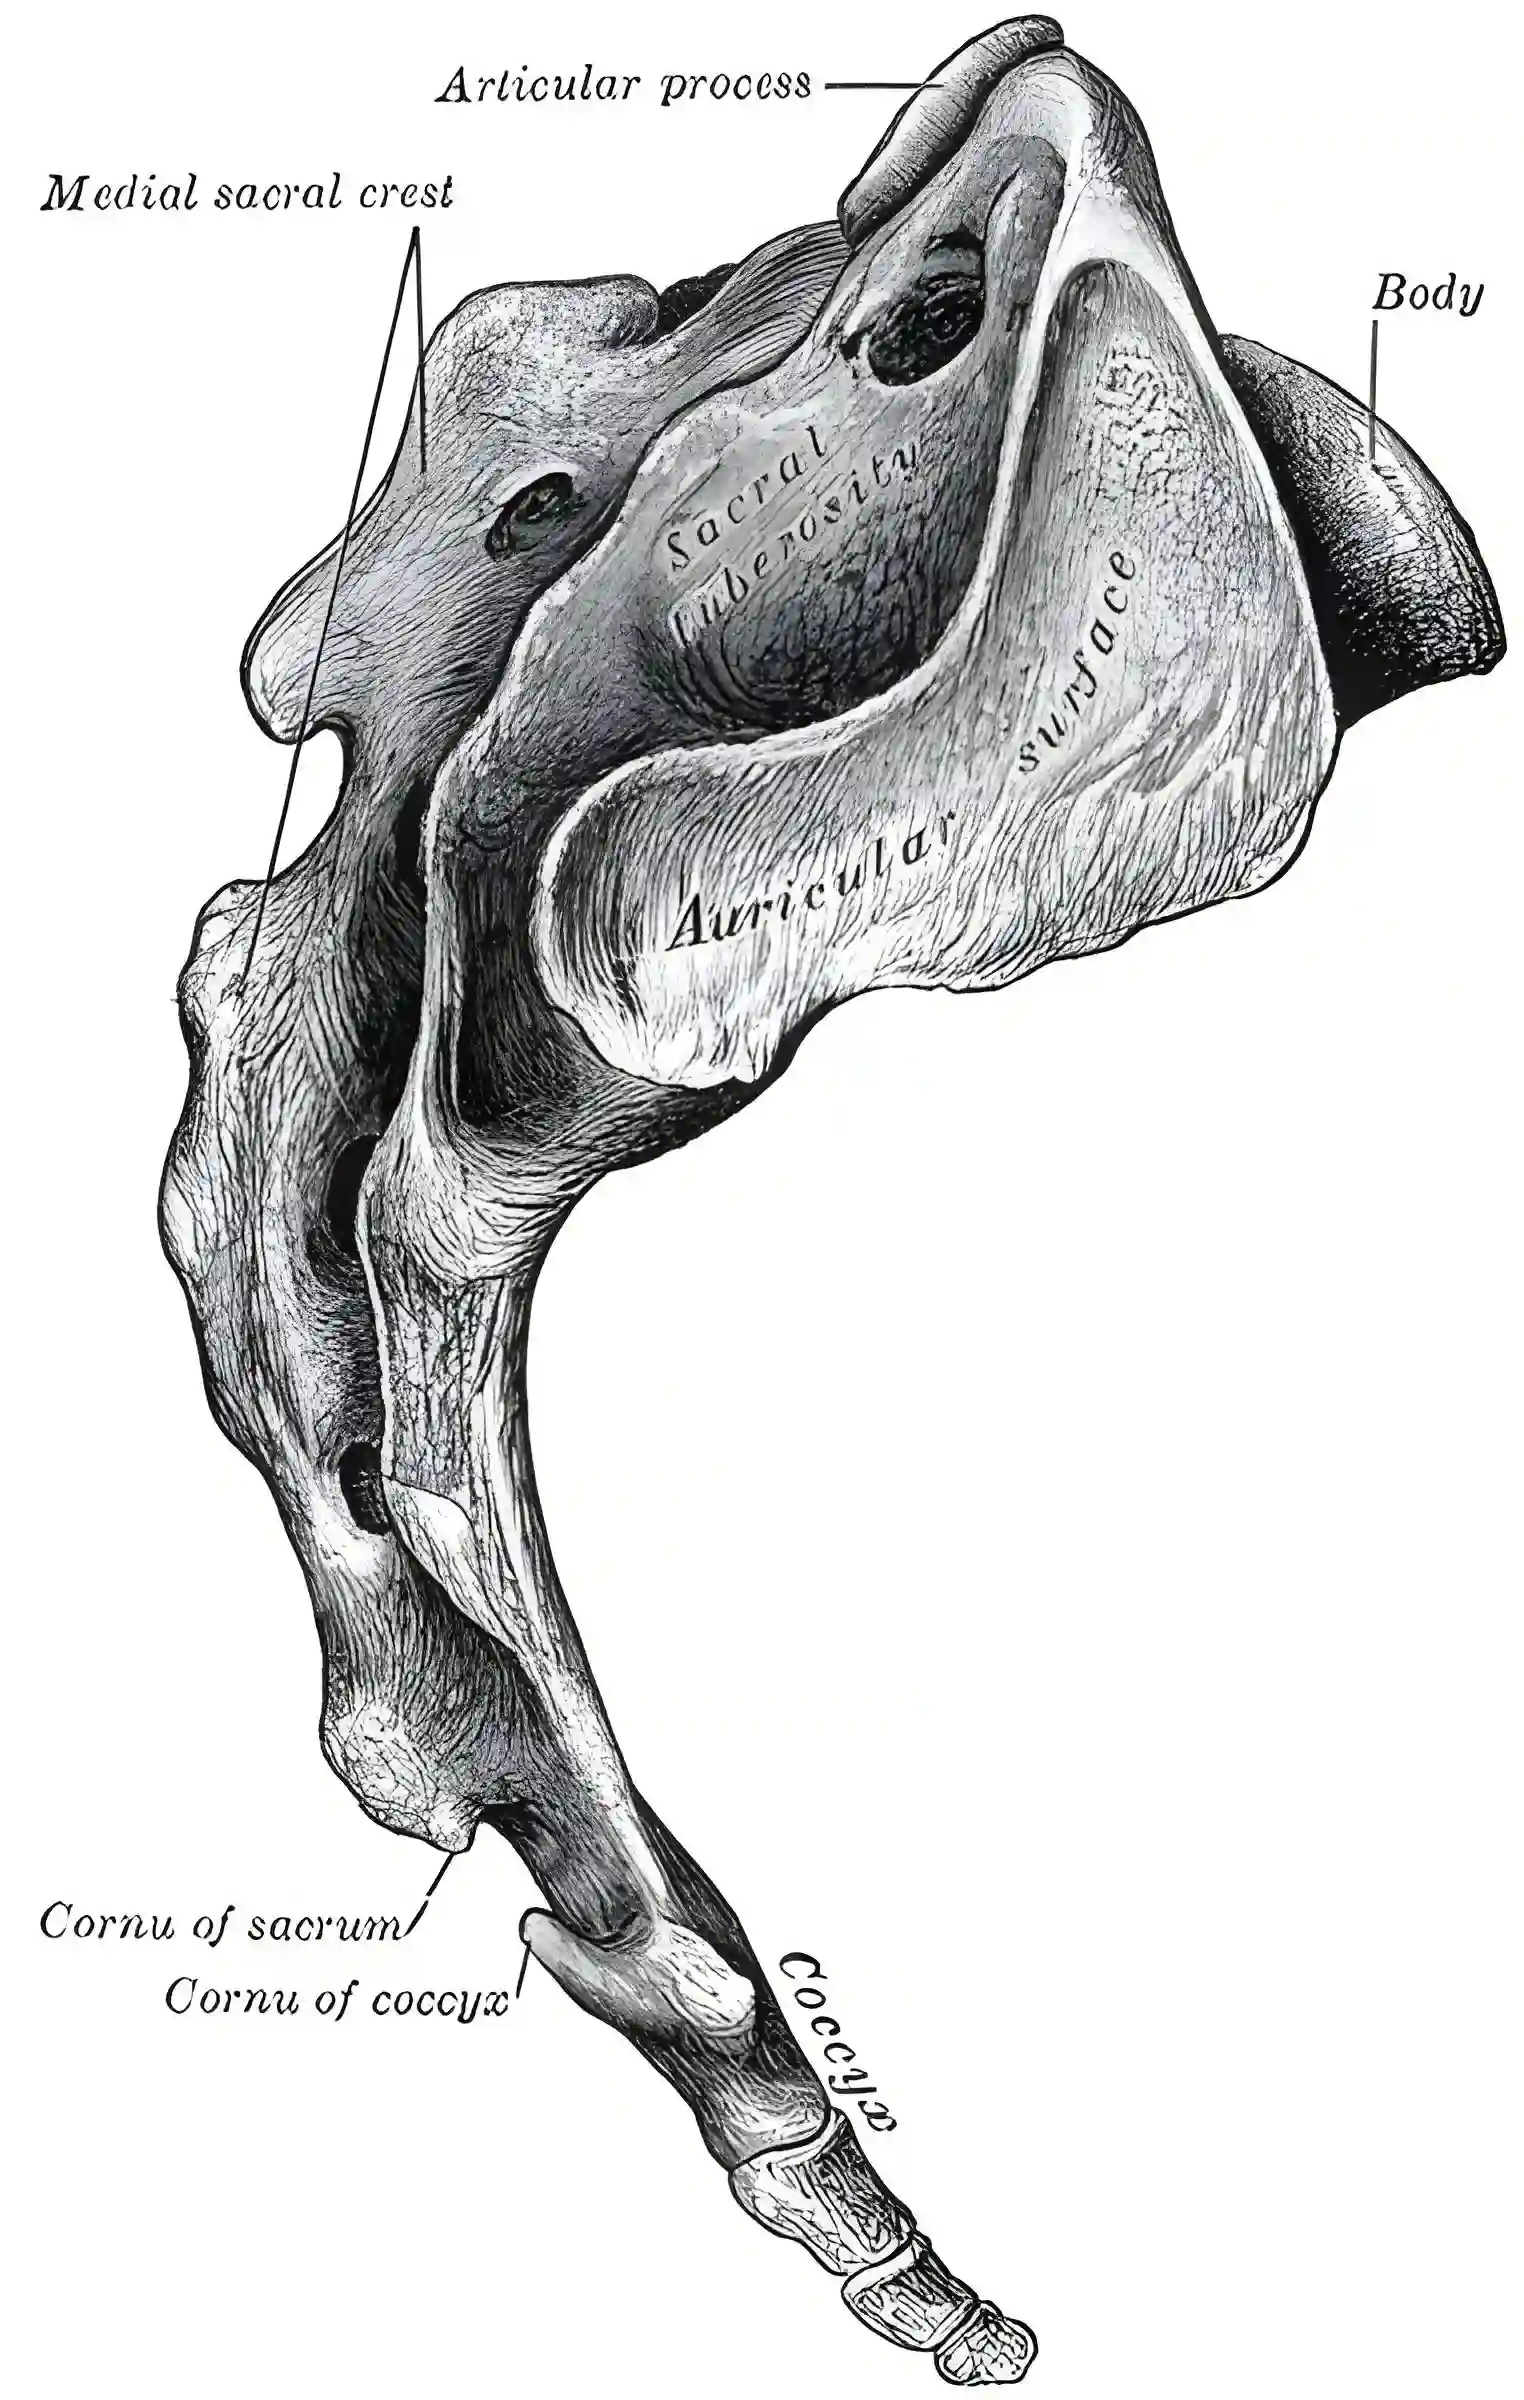

Os sacrum Fgure 95

Schematische Abbildung des Os sacrum. Abbildung adaptiert von Grays Anatomy Figure 95.